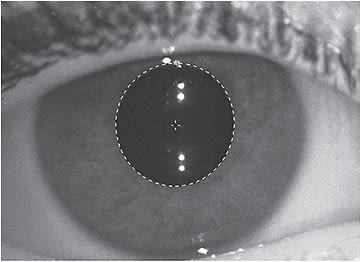

- Undercorrection of refractive error has no clinically significant benefit in slowing myopia (Wolffsohn et al, 2019) and may even lead to faster myopia progression (Chung et al, 2002; Adler et al, 2006). When a spherical soft multifocal lens is used as a means of optical correction for a patient, any residual toric prescription means that an optical meridian at the retinal (foveal) plane will experience defocus. This still qualifies as a form of undercorrection and may lead to faster progression of myopia than anticipated. When this residual astigmatism is mainly due to corneal astigmatism (Figure 1), the tear lens created by the GP center of a hybrid lens can provide optimal correction of central vision, thus mitigating this risk.

Figure 1. Clinically significant limbus-to-limbus corneal astigmatism. - Reducing relative hyperopic defocus at the peripheral retinal plane signals an eye to slow down its axial, and subsequent refractive, growth (Wildsoet et al, 2019). This finding has prompted researchers to evaluate the role of lower versus higher add powers in simultaneous-design multifocals on slowing the progression of myopia; they hypothesized that greater peripheral plus power in the lens leads to better control of myopia. Although children may not be able to tolerate add powers higher than 2.50D due to significant decreases in optical quality, multifocal hybrid lenses with center distance optics can be designed with add powers as high as +5.00D.